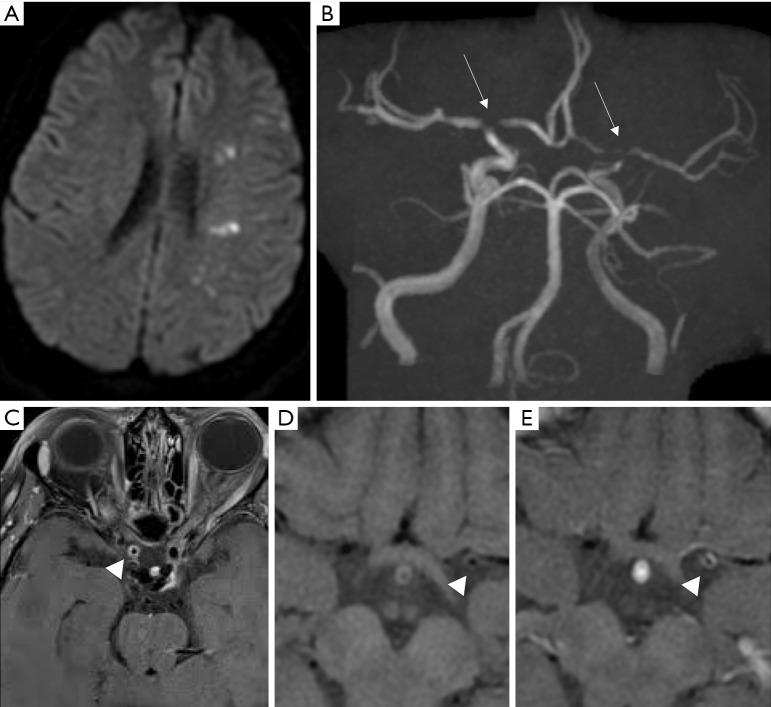

Figure 3.

Giant cell arteritis and intracranial vasculitis. A 72-year-old male with transient amaurosis of the right eye, headaches, and pain while chewing. No diabetes mellitus, no arterial hypertension, high sedimentation rate. DWI (A) demonstrates ischemic spots with restricted water diffusion in the left MCA territory. Intracranial stenoses on 3D Time-of-Flight (B, white arrows) of the bilateral terminal portion of the ICA, M1 and A1 segments are present. Post-contrast VW-MRI (C,E) compared to pre-contrast VW-MRI (D) shows circumferential vessel wall enhancement of the stenosed intracranial vessels (arrow head), in favour of a vasculitis. The biopsy of the temporal artery confirmed the diagnosis of giant cell arteritis. DWI, diffusion weighted imaging; VW-MRI, vessel wall MR imaging.